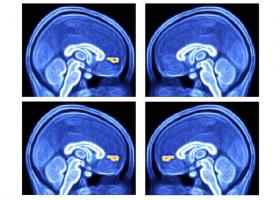

Cette équipe de bioingénieurs de l’ETH Zurich, experte dans l’exploitation des microrobots dans de nouvelles technologies, présente ici dans la revue Science, son dernier microrobot, tout à fait « minuscule ». Avec une application phare l’AVC, où le microrobot va délivrer le médicament exactement sur le site du caillot ou thrombus.